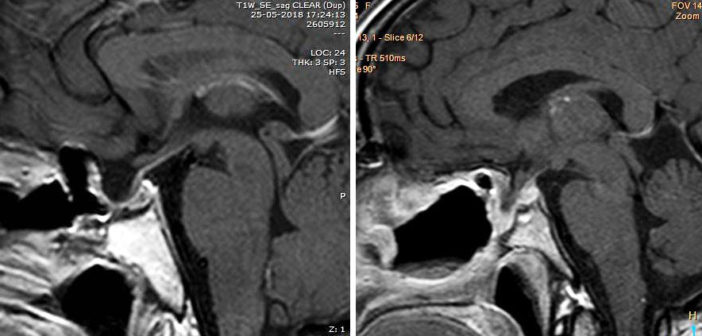

“Significa básicamente abordar la hipófisis a través de la nariz, por los orificios naturales del cuerpo, sin incisión. Usando como medio el endoscopio y dejando de lado el medio más clásico de la neurocirugía que es el microscopio”, explica el Dr. Jaime Pinto, neurocirujano del Hospital Clínico Regional de Concepción Dr. Guillermo Grant Benavente y director médico de la Clínica Biobío, quien además asegura que la inmensa mayoría de tumores de hipófisis son benignos, siendo el número uno el adenoma pituitario, el que podría considerarse el 70% de los tumores de base de cráneo.

Según el Dr. Pinto, las ventajas de la técnica son muchas: “En comparación con el microscopio, tiene ventajas claras respecto a la visualización, como es una cercanía a la anatomía mucho mayor, porque el endoscopio prácticamente llega a la silla turca”. Además, sostiene que esta técnica es reconocida mundialmente por su utilidad, por lo que se ocupa en todas partes y para todos los tipos de tumores. “Hay tumores especiales que uno tiene que hacer técnicas combinadas (transcraneano más cirugía endoscópica por la nariz), pero en general la cirugía endoscópica ha ido avanzando y prácticamente casi muy pocas cosas no se pueden sacar completamente con el endoscopio”, afirma.